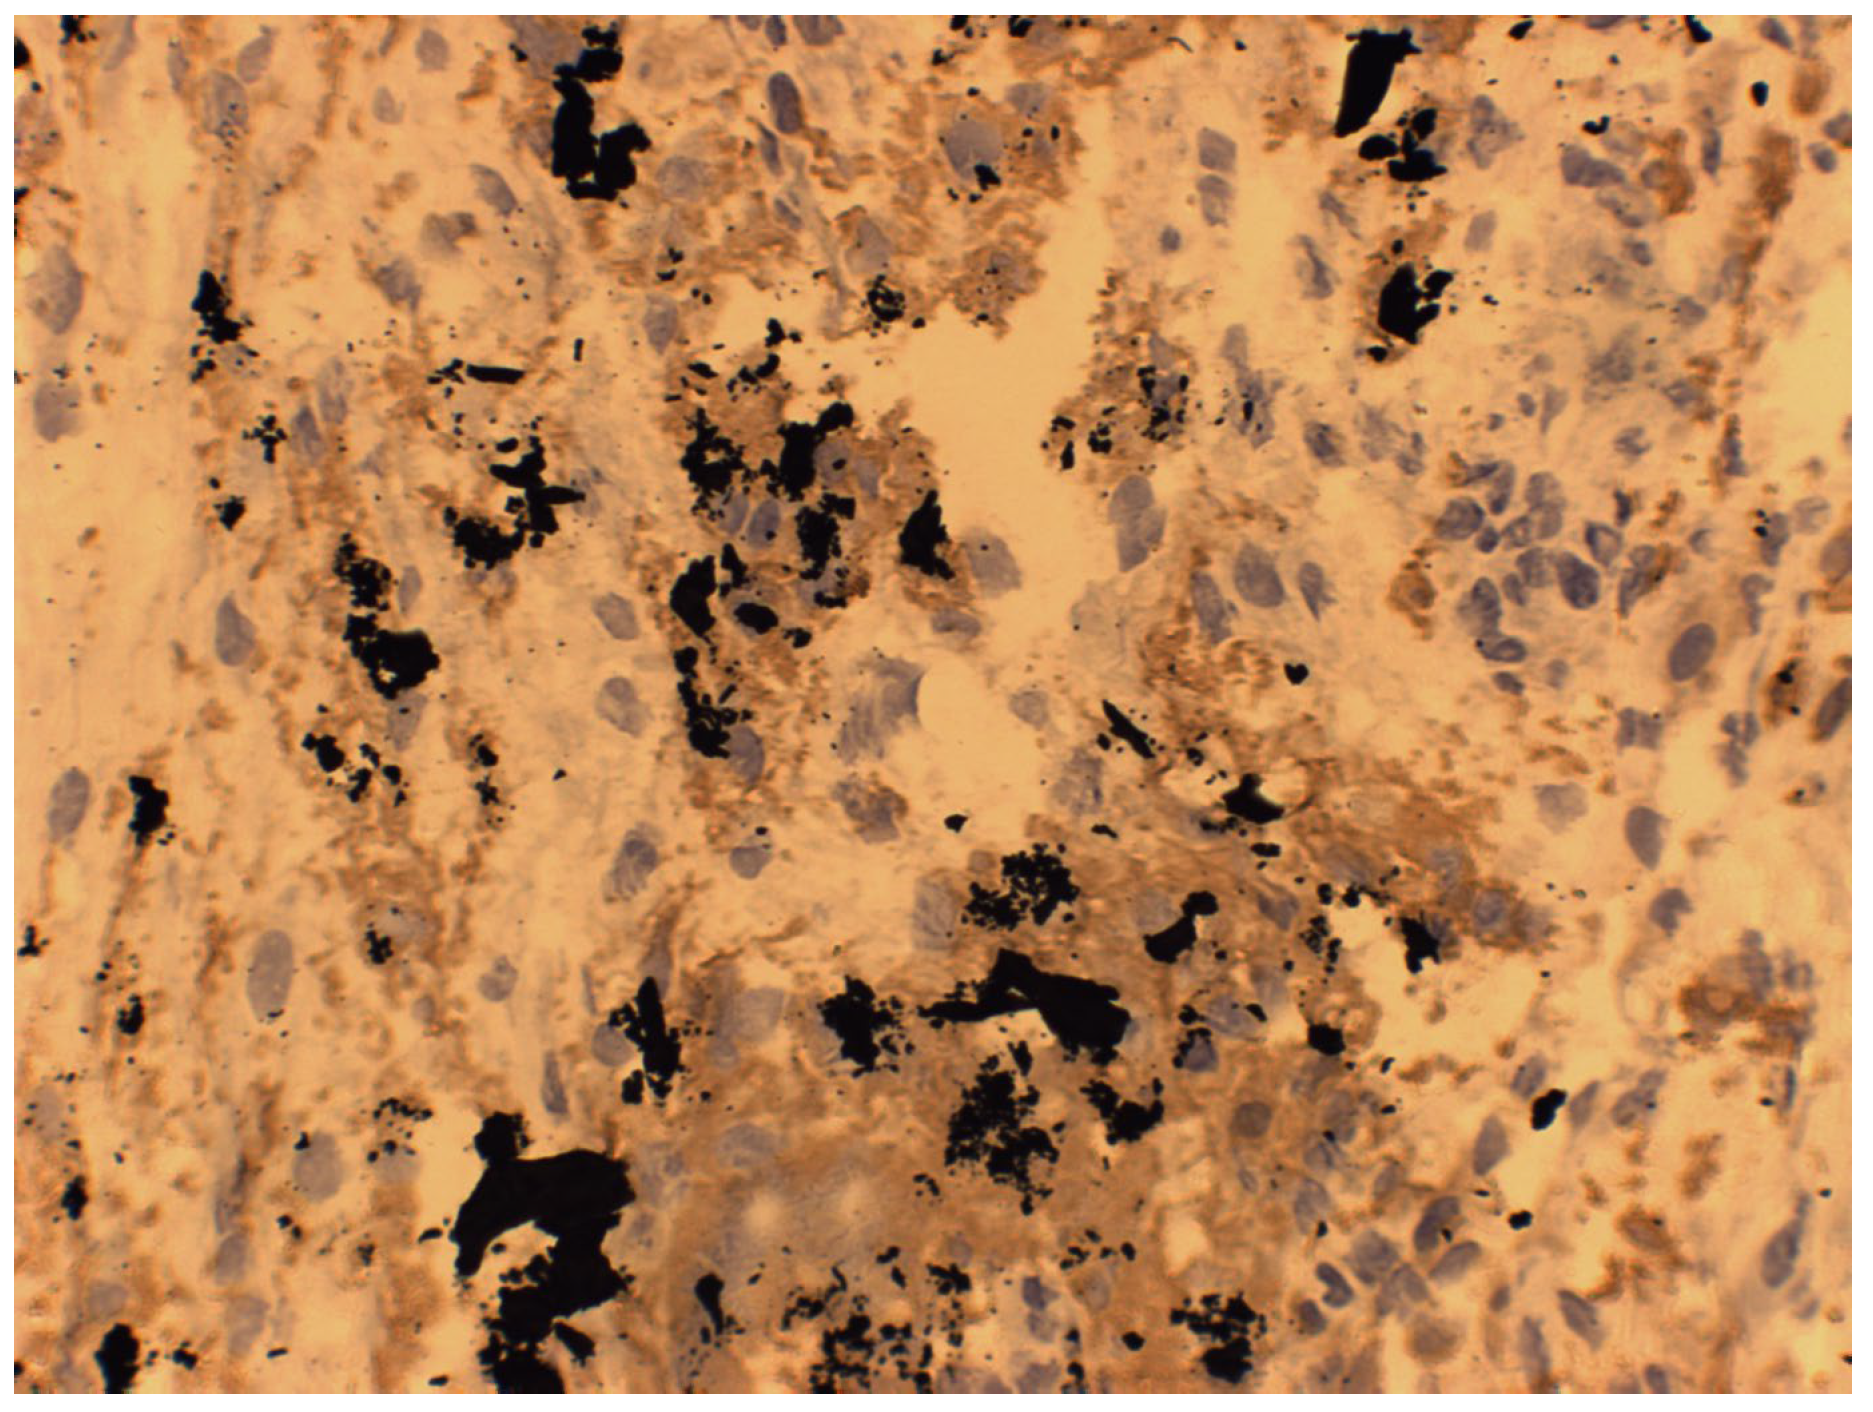

7. Macroscopic Observations of Interacted Surfaces of Removed Implants—Author Observations